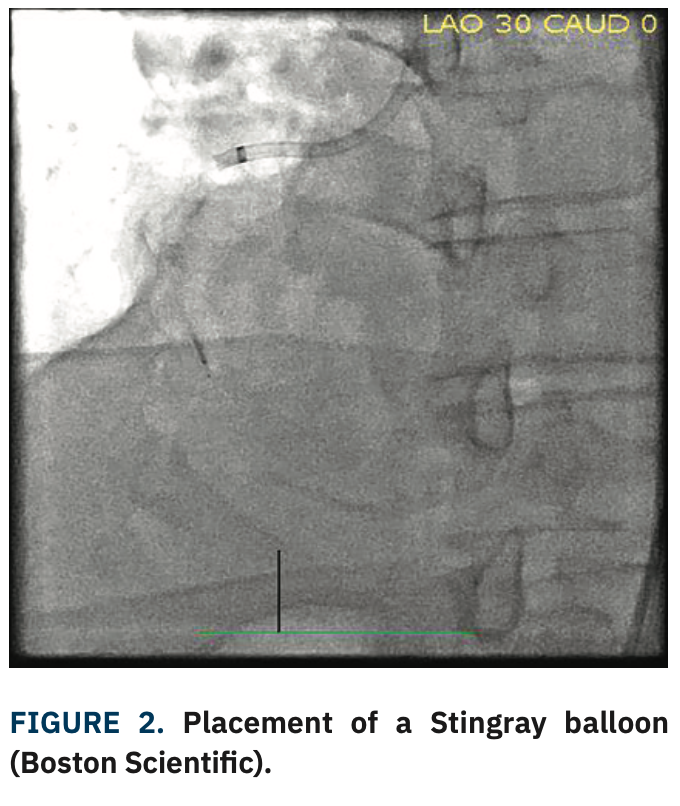

Bilateral femoral access was obtained with placement of an 8 French (Fr) sheath and 6 Fr sheath. An 8 Fr Amplatz Left (AL)-1 guide with side holes was used to engage the RCA. A 90 cm Extra Backup (EBU) 4 guide was used to engage the left main. Dual angiography demonstrated the mid-RCA occlusion (Figure 1, Video 1).

A Corsair Pro microcatheter (Asahi Intecc) was brought antegrade initially with a Gladius Mongo wire (Asahi Intecc); the wire crossed the proximal cap but entered the subintimal space. Both a Pilot 200 (Abbott Vascular) and Hornet 14 wire (Boston Scientific) failed to enter the true lumen distally. A Mongo wire was then advanced with a knuckle fashion to the distal landing zone, followed by the Corsair Pro microcatheter. The Mongo wire was removed and replaced with a Miracle 12 wire (Asahi Intecc), followed by removal of the Corsair Pro and placement of a Stingray balloon (Figure 2). The Miracle 12 wire was removed and a Hornet 14 wire was used to reenter the vessel. Subsequently, the Hornet 14 was removed and swapped for a Pilot 200 wire, which was advanced into the true lumen distally and confirmed on retrograde injection. The Stingray balloon was removed and replaced with a Corsair Pro microcatheter. The Pilot 200 was removed and replaced with a Sion Blue (Asahi Intecc). The Sion Blue was used to wire the distal posterior descending artery (PDA). The Corsair Pro microcatheter was removed. The RCA was pre-dilated with a 3.5 noncompliant balloon, followed by intravascular ultrasound (IVUS). After IVUS, the RCA was stented with 4.0 mm x 38 mm, 4.0 mm x 38 mm, and 4.0 mm x 32 mm Synergy drug-eluting stents (Boston Scientific), all of which were post-dilated with a 5.0 noncompliant balloon. Repeat IVUS showed no edge dissection and good stent apposition. Final angiography showed no residual stenosis (100% to 0%) and TIMI-3 flow distally (Figure 3, Video 2).